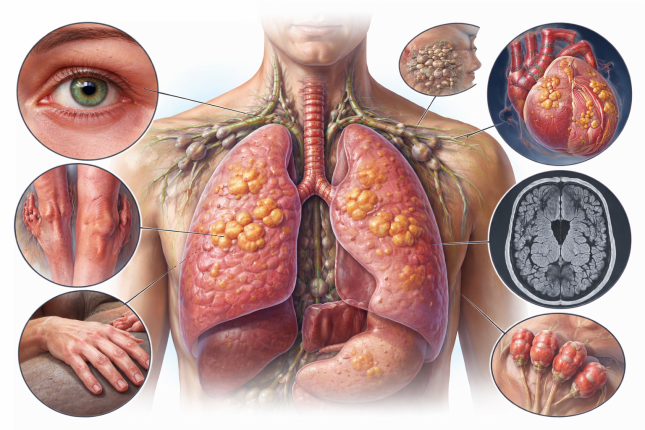

Саркоїдоз — це системне запальне захворювання, яке може уражати різні органи, але найчастіше — легені та внутрішньогрудні лімфатичні вузли. Назва «саркоїдоз» походить від грецького слова, що означає «схожий на м’ясо» і відображає характерний вигляд уражених тканин при цьому захворюванні.

Головна морфологічна ознака саркоїдозу — утворення дрібних вузликів запалення (гранульом) у тканинах. Особливість цих гранульом — відсутність гнійного або некротичного розпаду (на відміну від туберкульозу). Саме це є ключовою гістологічною ознакою, яку шукає лікар при мікроскопічному дослідженні.

Саркоїдоз — системне захворювання, тому часто вражає інші органи:

Очі: почервоніння, біль, порушення зору (увеїт) — у кожного четвертого пацієнта. Гострий увеїт потребує негайного лікування — ризик необоротної втрати зору!

Шкіра: характерні прояви — болючі червоні вузлики на гомілках (вузлувата еритема), фіолетово-синюшні щільні утворення на носі, щоках або вухах (люпус перніо).

Лімфатичні вузли: безболісне збільшення периферичних лімфовузлів.

Серце: порушення серцевого ритму, блокади, рідше — серцева недостатність. Серцевий саркоїдоз небезпечний ризиком раптової серцевої смерті!

Нервова система: параліч мімічної мускулатури (зазвичай з одного боку), рідше — менінгіт, ураження спинного мозку.

Суглоби та кістки: болі в суглобах, набряклість.

Печінка та селезінка: збільшення, порушення функції — виявляють у кожного п’ятого.